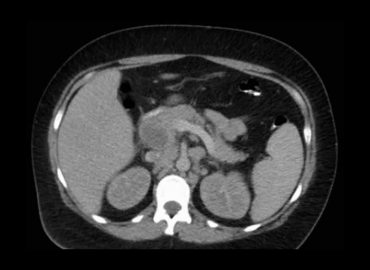

Dolor en FID y Leucocitosis.

Paciente de 39 años consulta por cuadro de diarrea, dolor abdominal, fiebre y perdida de peso (10kg) de 2 meses […]